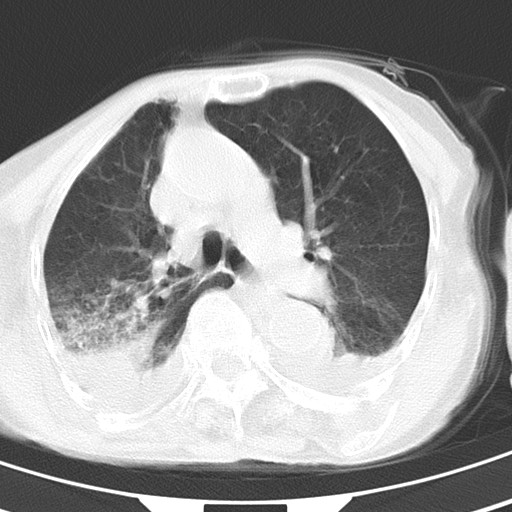

女,93岁,摔伤后检查。

右肺炎症,心功能不全伴双侧胸腔积液,右下肺膨胀不全,食管裂孔疝,冠脉钙化,心包少量积液,左侧肋骨骨折,请上传骨窗.

右侧锁骨\\肩胛骨骨折、右侧湿肺,心功能不全伴双侧胸腔积液,右下肺膨胀不全,左膈破裂或食管裂孔疝,冠脉钙化,心包少量积液,请上传骨窗.

右肺炎症,心功能不全伴双侧胸腔积液,右下肺膨胀不全,食管裂孔疝,冠脉钙化,心包少量积液,左侧肋骨骨折,右肩甲骨粉碎性骨折。93岁,高寿哇!

右肺炎症,心功能不全伴双侧胸腔积液,右下肺膨胀不全,食管裂孔疝,冠脉钙化,心包少量积液,左侧肋骨骨折,右肩甲骨粉碎性骨折。